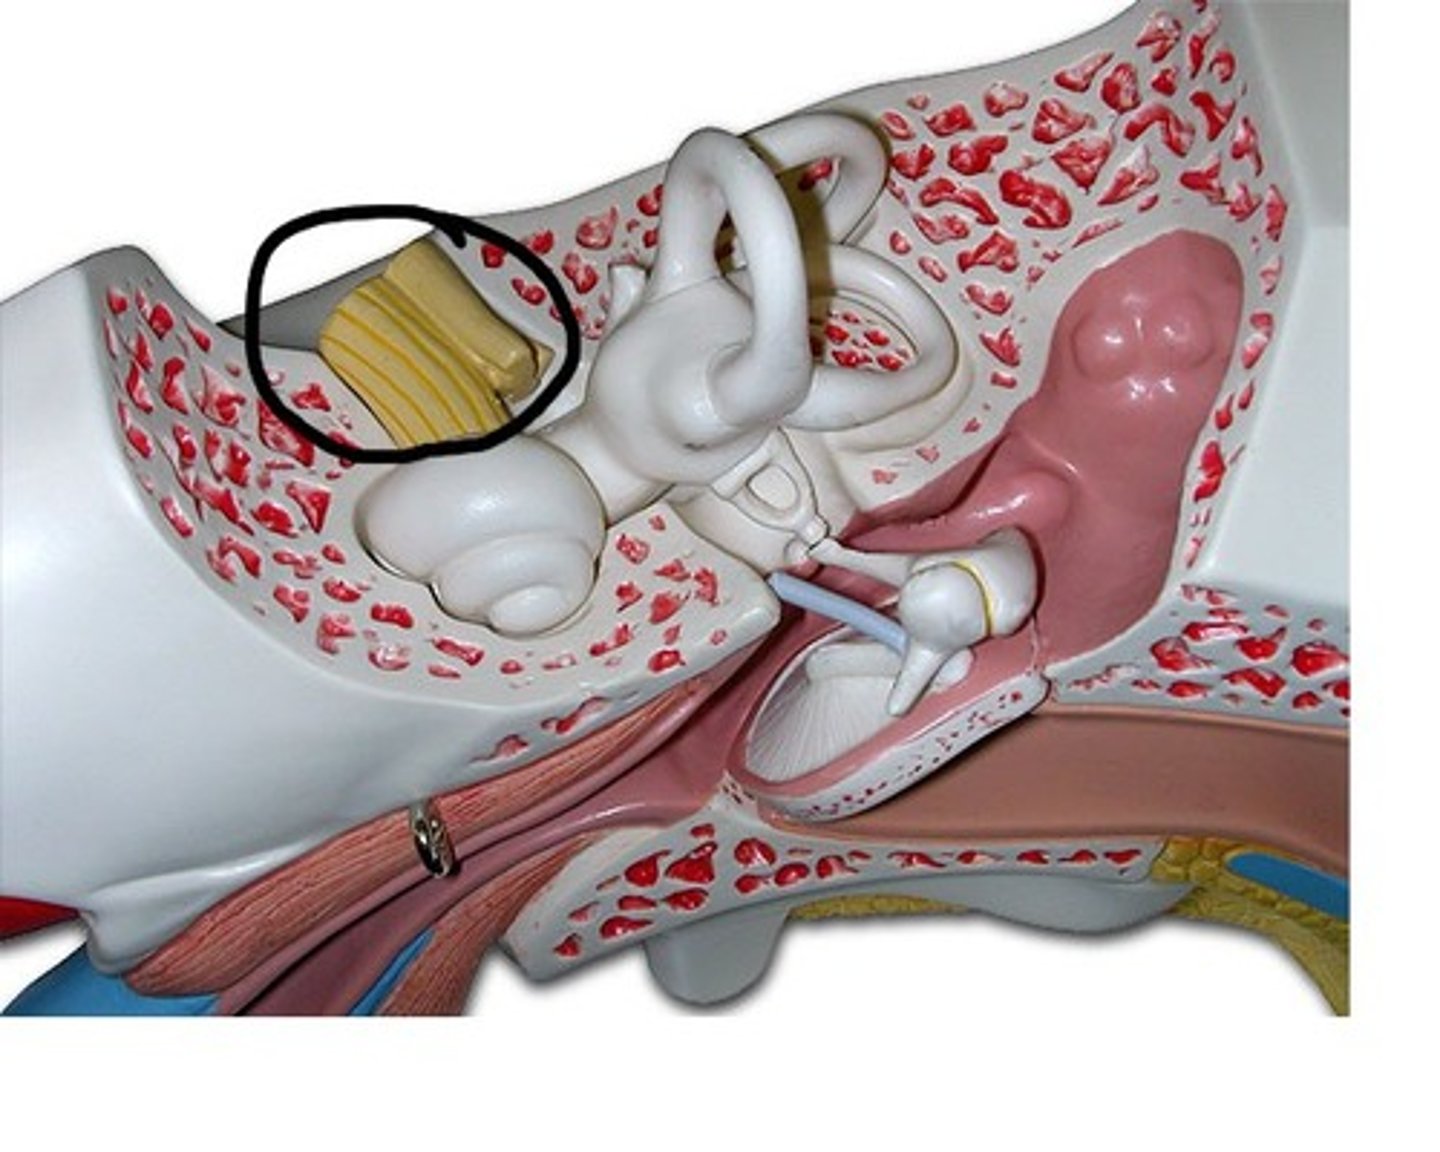

auditory tube

auricle (pinna)

cochlea

cochlear nerve

external auditory canal

incus

labyrinth (osseous + membranous)

(general structure, ignore arrow)

malleus

oval window

round window

scala tympani

section of cochlea

scala vestibuli

section of cochlea

semicircular canals

spiral organ (of corti)

section of cochlea

stapes

temporal bone

tympanic membrane

vestibular nerve

vestibule

vestibulocochlear nerve